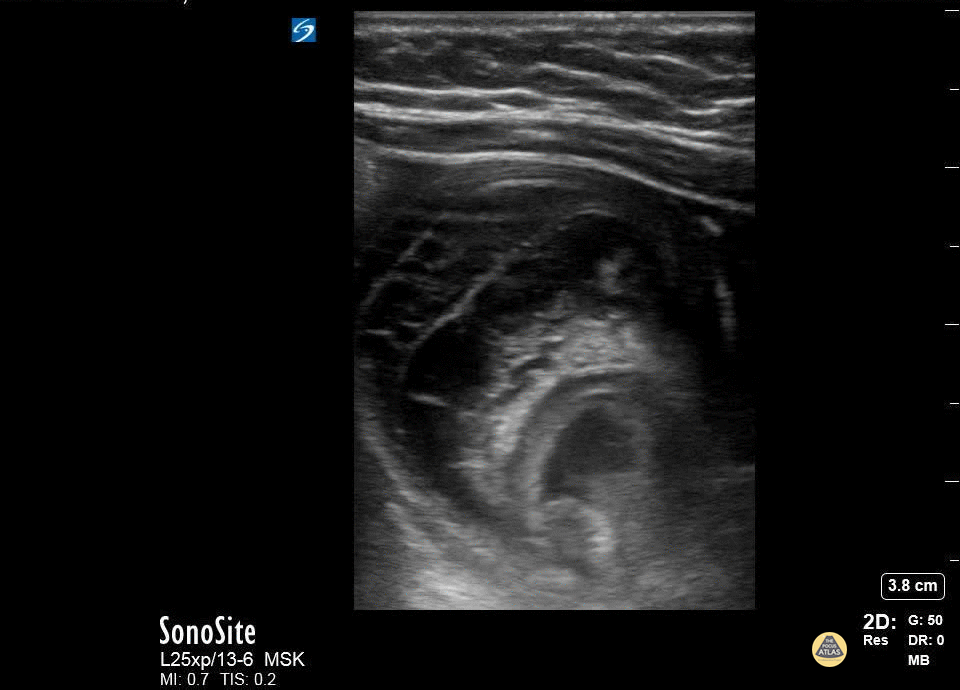

This is a transverse view of the right upper quadrant of an infant who presented with several days of worsening colicky pain. He had decreased appetite, activity and vomiting. Bedside ultrasound revealed evidence of intussusception with extensive surrounding bowel edema likely secondary to delayed presentation. Chris Heberer, DO EM PGY-3 CMU-Saginaw